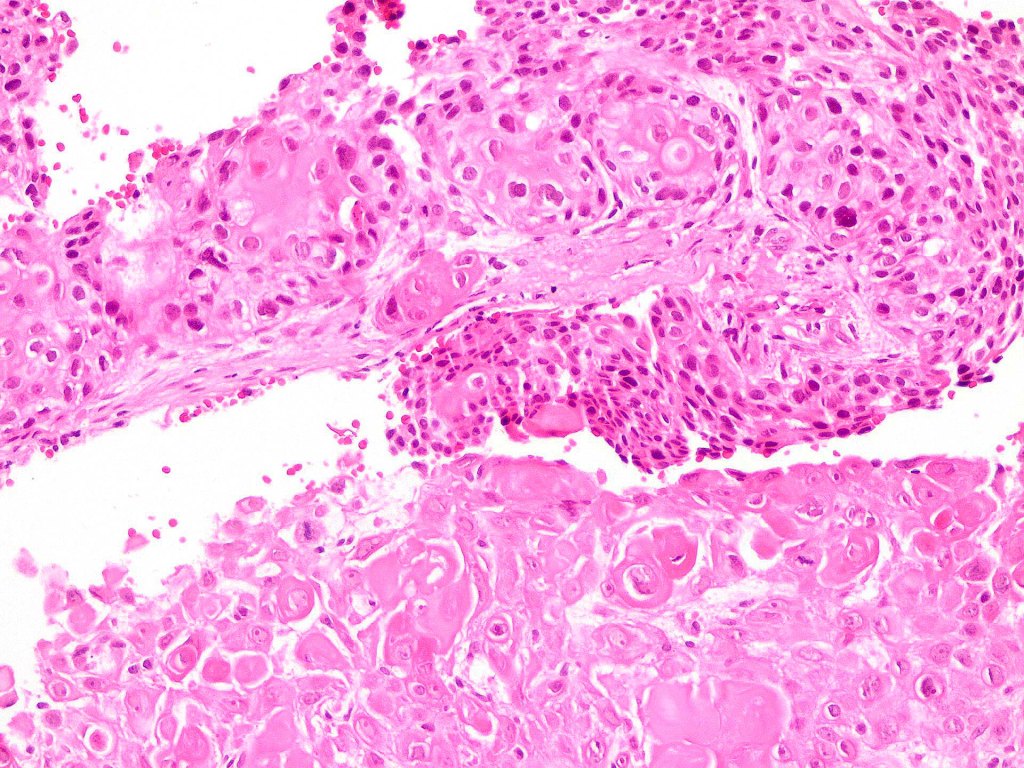

•Admixture of squamous carcinoma & pleomorphic spindled cell, osteoid, chondroid, MFH-like +/- osteoclast-like giant cells & rarely, smooth muscle, skeletal muscle, myofibroblastic or angiosarcomatous elements

•Epithelial component AE1/AE3, CK5/6 & p63 +ve;

•Mesenchymal element variable CD10, CD68, CD99 & lineage specific markers +ve; scattered cells may show weak keratin expression